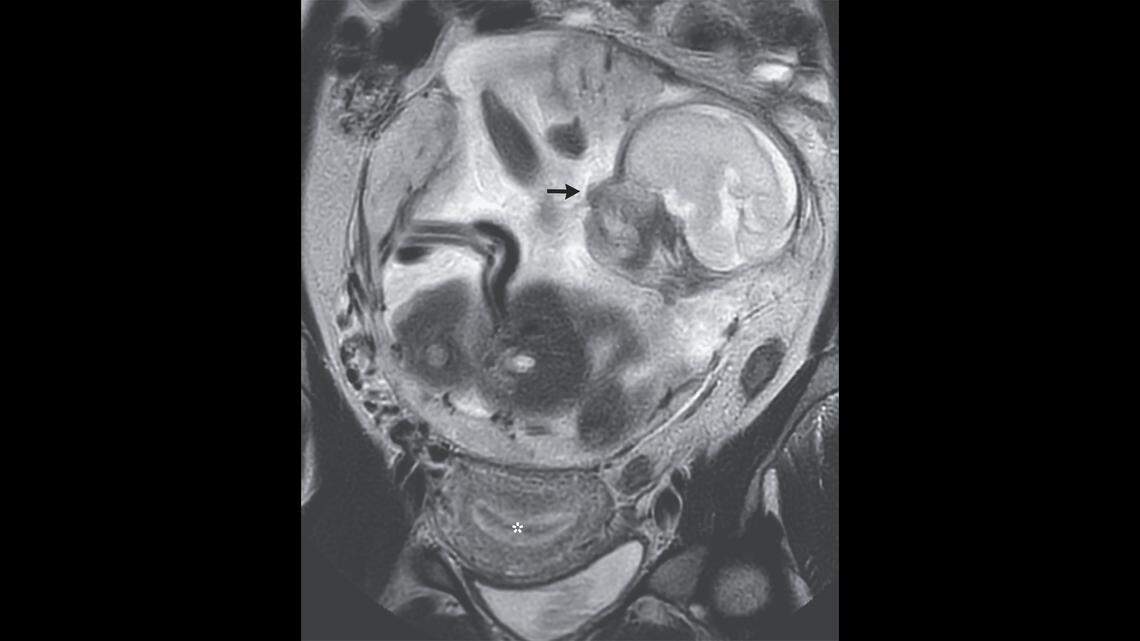

An MRI was taken of the woman’s abdomen and showed her uterus, marked by the asterisk, empty, and the fetus, marked by the black arrow, growing above, doctors said.

Based on the size and growth of the fetus, her doctors estimated the pregnancy to be 23 weeks along, nearly the end of the second trimester, according to the report.

The placenta, an organ that develops during pregnancy to surround a fetus and provide oxygen and nutrients, was attached to the woman’s peritoneum, a membrane that lines the abdominal cavity, instead of inside the uterus, doctors said.

Instead of the growth from the fetus creating a bump on the front of the woman’s body, the placenta was growing just above the sacral promontory, a bone on the back of the body that connects the bottom of the spine to the pelvis, according to the report.